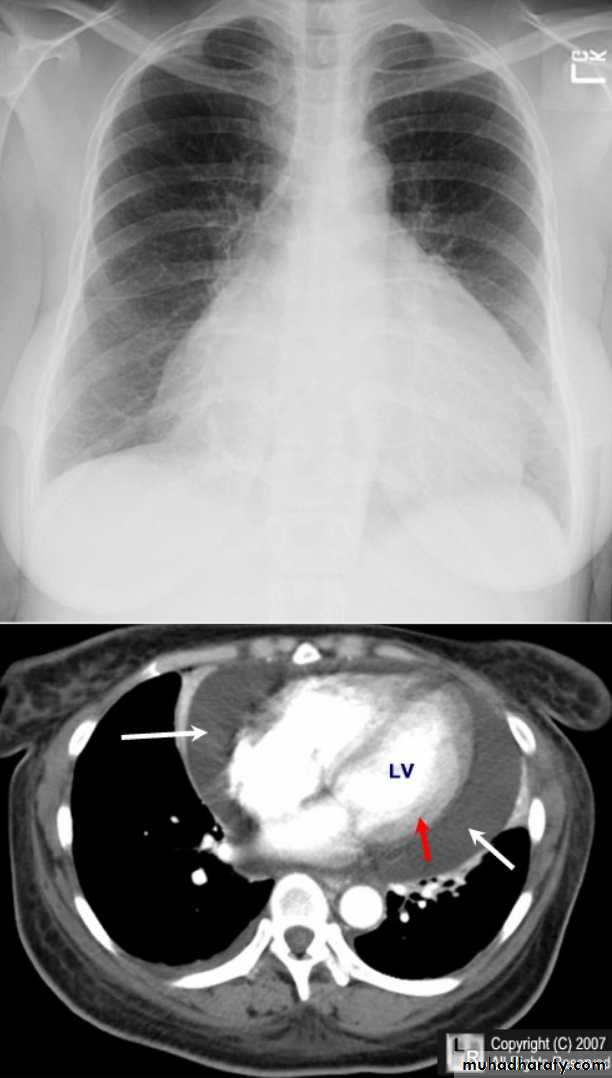

Pericardial effusion

occur when fluid collects in the pericardial space (a normal pericardial sac contains approximately 30-50 ml of fluid).radiographic features

Plain radiograph

a very small pericardial effusion can be occult on plain film, greater than 200 ml required to be visible radiographicly.

there can be globular enlargement of the cardiac shadow giving a water bottle configuration; known as Globe shape heart or pumpkin shape heart .